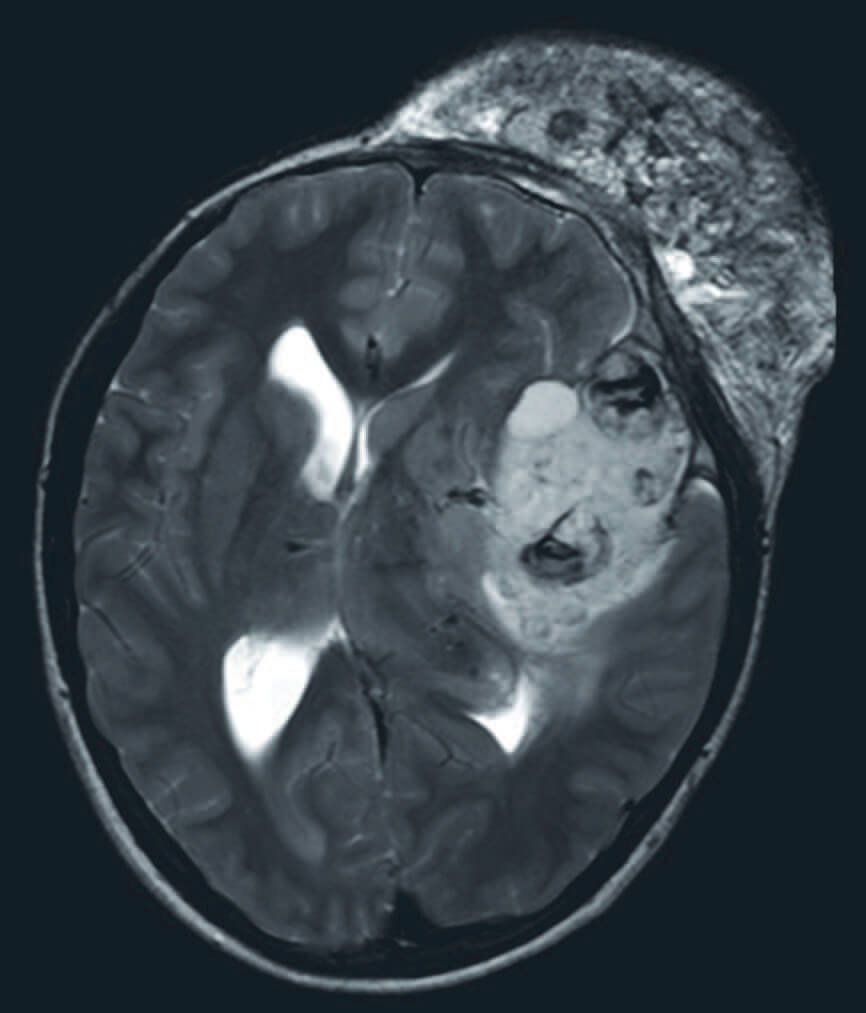

Neuro